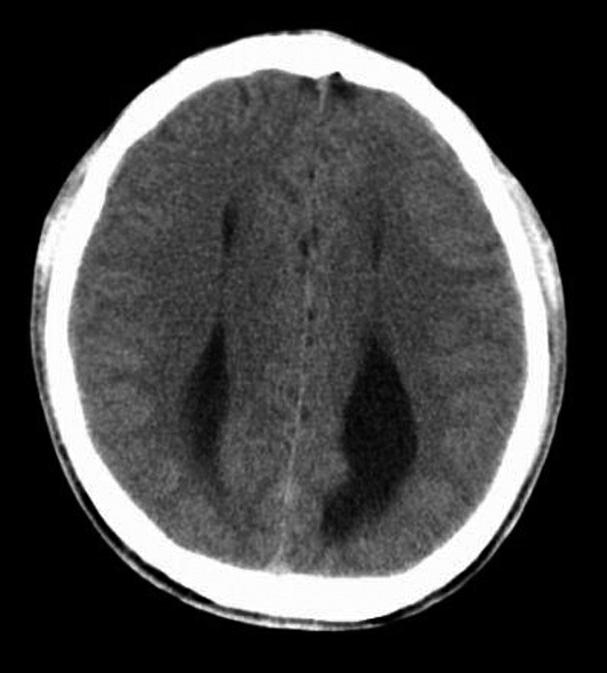

第三脑室正常成人前后径约12mm,左右宽约5mm,上下径也约为12mm。侧脑室后角两侧有时大小不等,右侧后角上下径约为38mm,左右径约为20mm;左侧后角上下径约为28mm,左右径约为15mm。测量双侧侧脑室前角间径与同平面脑横径的比值(R),正常平均值为30%。轻度扩大时为31%~39%,中度扩大为40%~46%,重度扩大时>47%。脑积水或脑萎缩等病理情况下脑室系统会扩大。不同年龄组正常脑室系统测量值存在差异,整体表现出测量值随着年龄增大而增大的趋势(图1-2-83、图1-2-84)。

图1-2-83 第三脑室测量

a线.第三脑室前后径;b线.第三脑室宽径

图1-2-84 侧脑室测量

R=双侧侧脑室前角间径(a)/同平面脑横径(b)